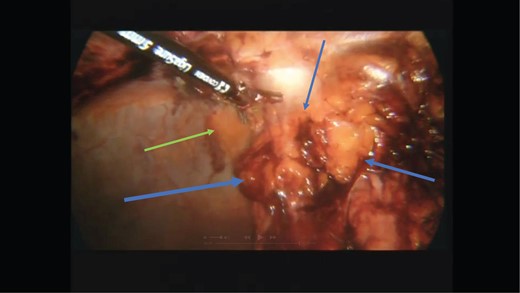

After an extensive discussion with the patient and his wife he agreed to a diagnostic laparoscopy with a view to reducing the hernia and repairing the mesenteric defect. Intra-operatively there was no internal hernia. A mass was seen in the epigastrium on the anterior abdominal wall (Fig. 3). The lesion could not be mobilized laparoscopically so the decision was made to convert to a laparotomy (Fig. 4). The lesion in the anterior abdominal wall was then mobilized and excised.

Laparoscopic view of the lesion (blue arrows) on the anterior abdominal wall (green arrow).